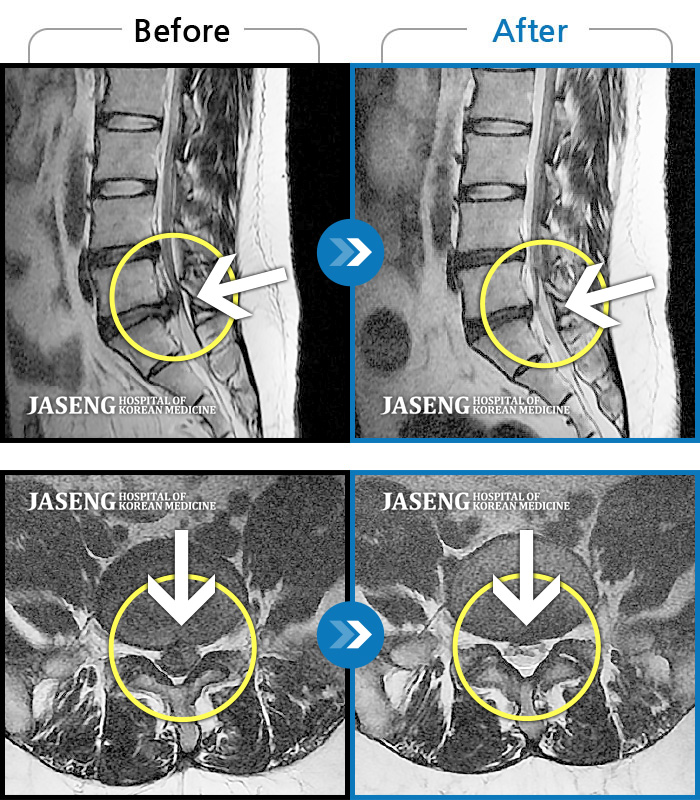

ȯںп Ǹ ǿ ԿǾ, ο ġ ۿ Ƿ ġḦ Ͻñ ٶϴ.